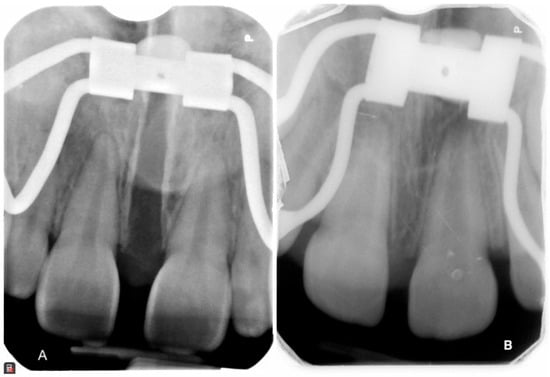

3. The Results of the Treatment